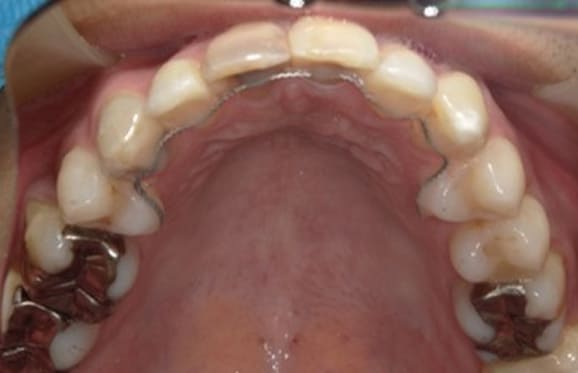

● 歯根が折れ保存不可の歯を抜歯して、そのスペースに八重歯を並べた症例

藤沢デンタルオフィスの虫歯や破折で抜歯後の部分矯正